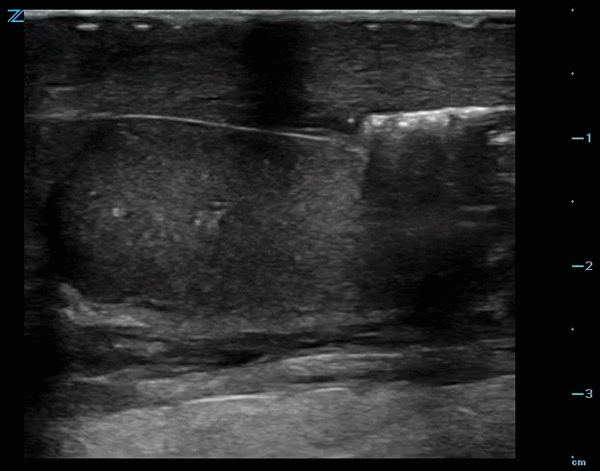

A bedside testicular ultrasound was performed:

Note scrotal skin thickening, and dirty shadowing suggestive of subcutaneous air.

Diagnosis: Fournier’s gangrene.

OR report: extensive necrotizing fasciitis of entire right hemiscrotum, half of left hemiscrotum right pre-pubic area/base of penis and perineum with sparing of bilateral testicles.